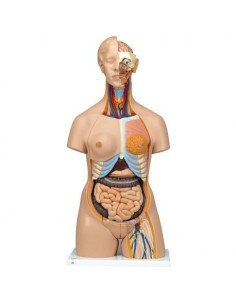

3B Scientifique, torse bisexuel japonais, décomposable en 18 parties B32/4